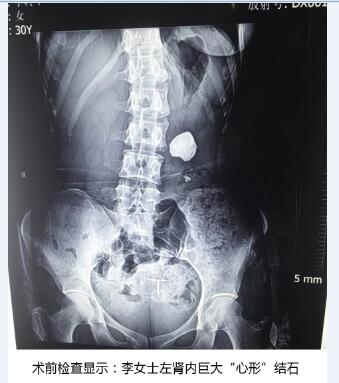

谈起过去这一年,三十岁的李女士唏嘘不已。多年前公司体检时发现左肾有轻微多发肾结石。十年来,因为没痛没痒的,她就没在意,存有侥幸心理,认为平时多运动,多喝一些水,注意饮食清淡,就可以把结石排出去。直到半个月前,她感到左腰部时常有剧烈的胀痛感,经常反复高烧,出现血尿、感染症状,且越来越重。到医院检查,检查结果着实把给她和医生们吓坏了,B超检查报告显示李女士左肾内结石几乎充满了整个肾,形似一颗“心形”。为了取出结石、保住左肾,她在家乡奔走求医,寻访多家大型医院,都告诉她需做1-2次开放手术,且没法保证取净结石。终她通过朋友打听到天津百信医院,并抱着极大希望赶到该院。

天津百信医院接诊了该患者,经检查发现,患者左肾肾盂充满了结石,直径达到5.5cm,结石几乎充满整个肾体,犹如一颗硕大的“心形”,并发左肾重度积水,左肾随时有坏死可能!